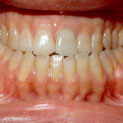

En la imagen intraoral se confirma el prognatismo mandibular, una oclusión en clase 3. Mordida de borde a borde con cierta asimetría en la que se aprecia una desviación de la línea media de casi dos o tres milímetros hacia la izquierda.